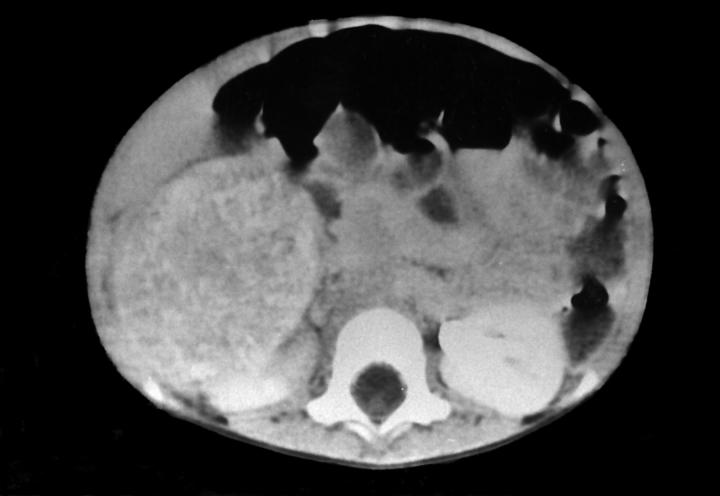

- MRI: hypointensity on T1 weighted image with rapid enhancement and hyperintensity on T2 weighted image (Intern Med 1995;34:1168)

Gross images